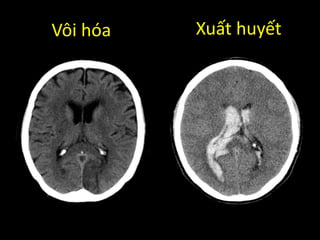

Vôi hóa Xuất huyết

Phân biệt vôi hóa hay xuất huyết?

VÔI HÓA

• Đối xứng

• Không có phù não

• Không có hiệu ứng

choáng chỗ

• Đậm độ: > 120 Hu

XUẤT HUYẾT

• Không đối xứng

• Có phù não xung quanh

• Có hiệu ứng choáng chỗ

• Đậm độ: 40-90 Hu

Phân biệt vôihóa hay xuất huyết? VÔI HÓA • Đối xứng • Không có phù não • Không có hiệu ứng choáng chỗ • Đậm độ: > 120 Hu XUẤT HUYẾT • Không đối xứng • Có phù não xung quanh • Có hiệu ứng choáng chỗ • Đậm độ: 40-90 Hu